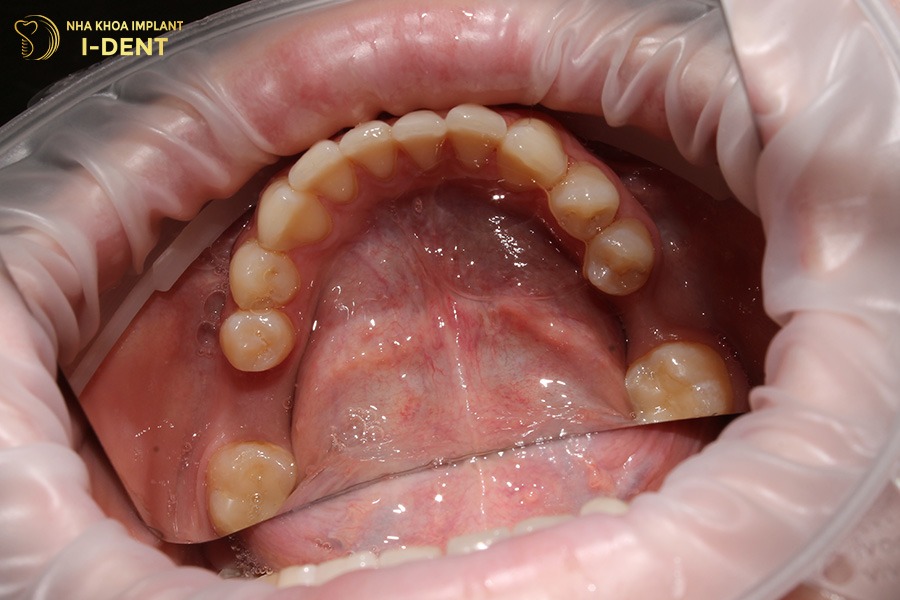

- Trồng răng Implant: Là phương pháp hiện đại nhất, cấy trực tiếp trụ titanium vào xương hàm để thay thế chân răng thật, sau đó gắn mão sứ lên trên. Implant giúp phục hồi gần như hoàn toàn chức năng ăn nhai, ngăn tiêu xương hàm và mang lại cảm giác ăn nhai tự nhiên như răng thật.